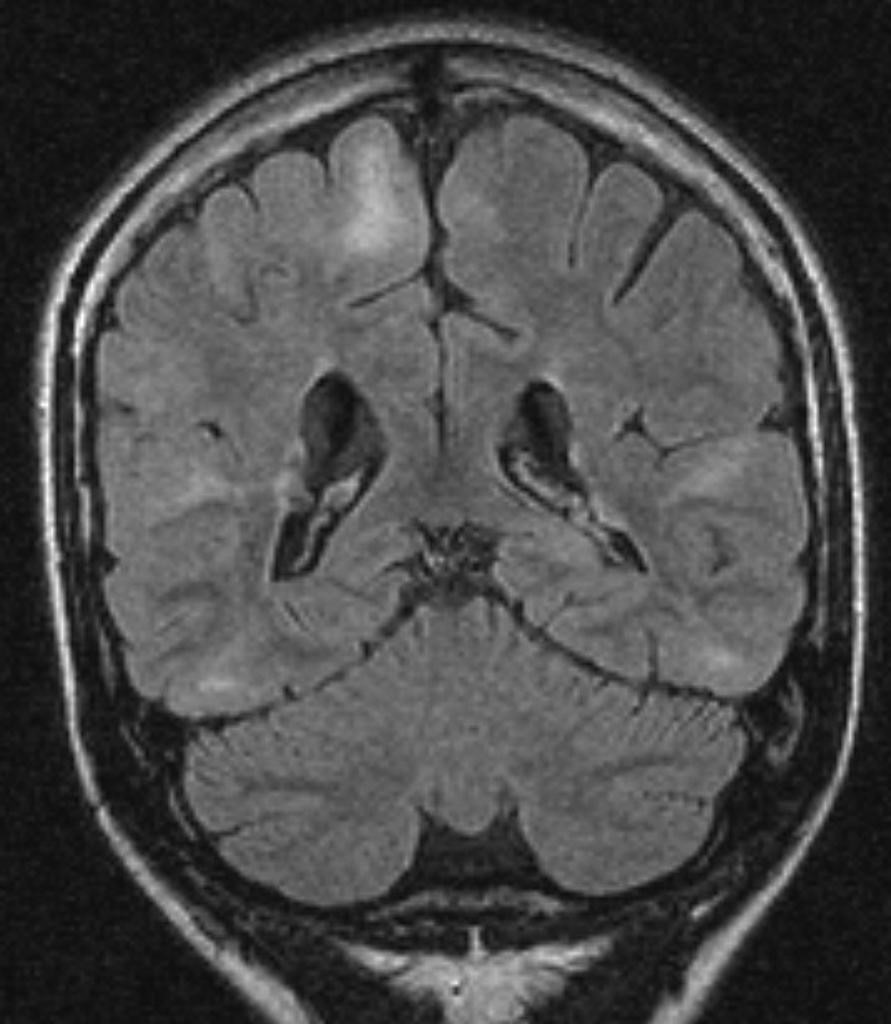

Voici une coupe de l’IRM cérébrale (coronale FLAIR) réalisée chez Simon :

Question 7 : Interprétez-la.

Absence de croissant sous-dural à l’IRM

À distance de l’AVC, on devrait voir des zones de nécrose de la substance blanche

Pas de déviation de la ligne médiane, pas d’engagement sous-falcoriel, pas d’effet de masse sur les ventricules latéraux

Les images en hypersignal correspondent à des tubers corticaux

Absence de collection bien délimitée à l’IRM